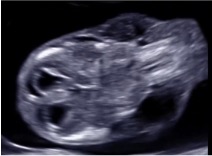

Guida al Counselling di Gennaio 2026: igroma cistico

vi presentiamo la guida al counseling di Gennaio 2026 sull’igroma cistico.